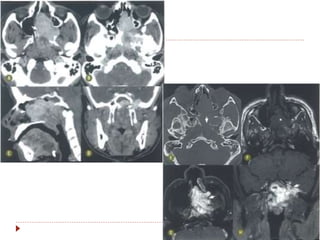

Laringe  Achados clínicos Rouquidão  Tosse crõnica, dispneia, disfagia.  CEC: 95-98%  60% na glote  30-40% supraglote  <5% subglote  Tabagismo e etilismo

 CEC: 95-98%

 60% na glote

 30-40% supraglote

 <5% subglote

 Tabagismo e etilismo